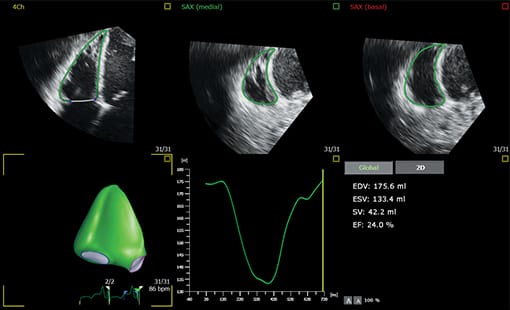

Evolving from Philips HeartModel, Dynamic HeartModel provides more critical capabilities in addition to LV and LA volumes to expand your clinical use and increase diagnostic confidence through 3D echocardiography technology. The Dynamic HeartModel tracks every frame over the cardiac cycle using 3D speckle technology. The moving contours of LA and LV borders and waveforms, additional LV, LA indexes and LV mass measurements provide a holistic view of the left heart function. The LV wall motion and the linkage between the LV and LA volume change over the heart cycle in order to increase your diagnostic confidence. In addition, the multi-beat selection and results average make the heart function evaluation more reliable than single beat, being ideal for arrhythmia or atrial fibrillation patients.

Boost your confidence in cardiac quantification during everyday workflows with HeartModel. This intuitive and validated 3D tool provides robust, reproducible ejection fraction (EF) in just seconds. What’s more, HeartModel is the only validated tool to provide simultaneous LV and LA volumes. It helps you easily characterize LA volume – shown to be an indicator of cardiovascular outcomes – to yield additional clinical information with no extra time or steps.

This study compared quantification between 2D and Live 3D HeartModel and demonstrated a 82% time savings for HeartModel when using the automated capability, and 63% time savings when minor edits were required.